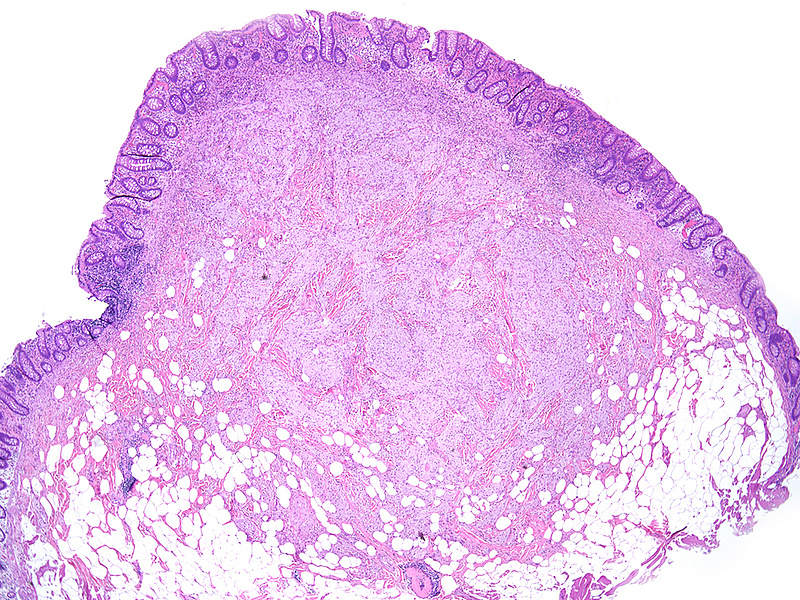

A 55-year-old male underwent endoscopy for large bowel cancer screening. A submucosal lesion was identified within the coecum and removed by snare polypectomy.

Histologically, we saw a submucosal proliferation of solid nests and ribbons of round to polyhedral cells, measuring approximately 6 mm in largest diameter (Panels A-B). The neoplastic cells generally contained small, uniform nuclei with inconspicuous nucleoli and abundant granular eosinophilic cytoplasm. They were separated by fibrous septa, which contained few inflammatory cells, mostly lymphocytes and few eosinophils (Panel C). In some areas, the neoplastic cells demonstrated cell spindling, still keeping the cytoplasmic features described above (Panel D). The lesion was ill-defined at the base, showing an infiltrative pattern into the surrounding adipose tissue within the submucosal layer (Panels E-F). The neoplastic cells were positive for PAS and strongly immunoreactive for S100-protein (Panels G-H), yet negative for keratin, CD117, DOG-1, and muscle markers, prompting final diagnosis of colonic granular cell tumour.

Granular cell tumors are common lesions in subcutaneous tissue. Gastrointestinal pathologists may encounter this form of peripheral nerve sheath tumour mainly in the oesophagus. In the colorectum, granular cell tumours prevail on the right side (coecum, around the ileocoecal valve, and within the ascending colon). On low power they are either infiltrative or well-defined, involving either the mucosa, submucosa (most common), or both. The cells are characteristically positive for PAS and S100-protein, but may also show positivity for SOX-10, NSE, and synaptophysin.